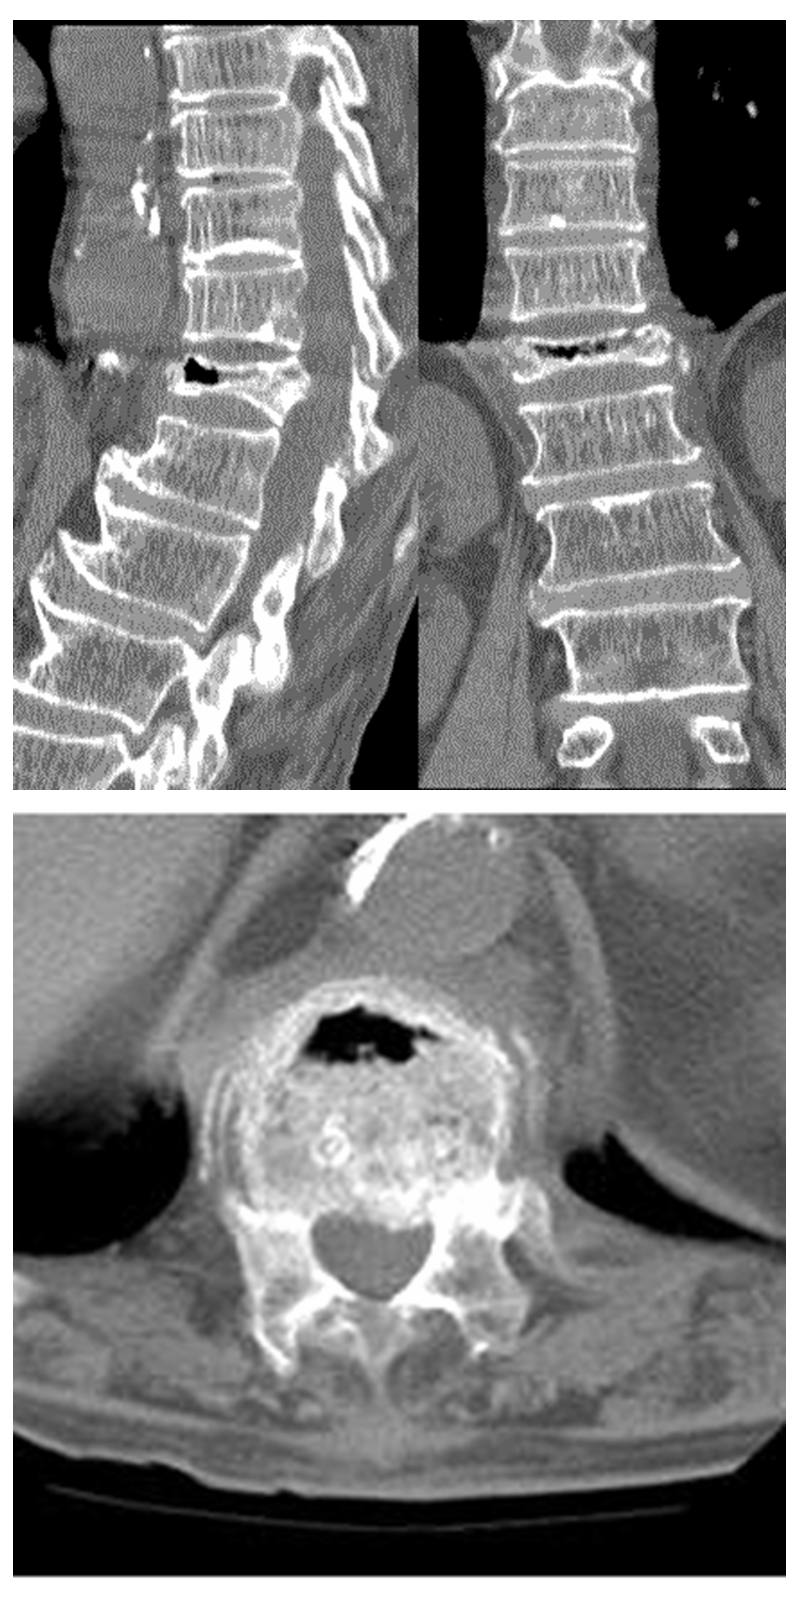

③在CT片上:矢状位和冠状位可见椎体内存在裂缝。与Xray片相比,裂隙更加不均匀、不规则;其诊断率较X平片更高;

当椎体裂隙周围坏死的骨组织逐渐增加,发生硬化,这会让术者在手术中穿刺到该部位时,常感觉阻力非常大,当穿刺针尖到达“裂隙”内时,有“落空感”。